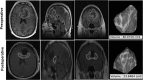

Introduction: Surgery is first-line therapy for glioblastoma, and there is evidence that gross total resection is associated with improved survival. Gross total resection, however, is not always possible, and relationships among extent (percent) of resection (EOR), residual volume (RV), and survival are unknown. The goals were to evaluate whether there is an association between EOR and RV with survival and recurrence and to establish minimum EOR and maximum RV thresholds.

Methods: Adult patients who underwent primary glioblastoma surgery from 2007 to 2011 were retrospectively reviewed. Three-dimensional volumetric tumor measurements were made. Multivariate proportional hazards regression analysis was used to evaluate the relationship between EOR and RV with survival and recurrence.

Results: Of 259 patients, 203 (78%) died and 156 (60%) had tumor recurrence. The median survival and progression-free survival were 13.4 and 8.9 months, respectively. The median (interquartile range) pre- and postoperative tumor volumes were 32.2 (14.0-56.3) and 2.1 (0.0-7.9) cm(3), respectively. EOR was independently associated with survival (hazard ratio [HR], 0.995; 95% confidence interval [CI]: 0.990-0.998; P = .008) and recurrence (HR [95% CI], 0.992 [0.983-0.998], P = .005). The minimum EOR threshold for survival (P = .0006) and recurrence (P = .005) was 70%. RV was also associated with survival (HR [95% CI], 1.019 [1.006-1.030], P = .004) and recurrence (HR [95% CI], 1.024 [1.001-1.044], P = .03). The maximum RV threshold for survival (P = .01) and recurrence (P = .01) was 5 cm(3).

Conclusion: This study shows for the first time that both EOR and RV are significantly associated with survival and recurrence, where the thresholds are 70% and 5 cm(3), respectively. These findings may help guide surgical and adjuvant therapies aimed at optimizing outcomes for glioblastoma patients.